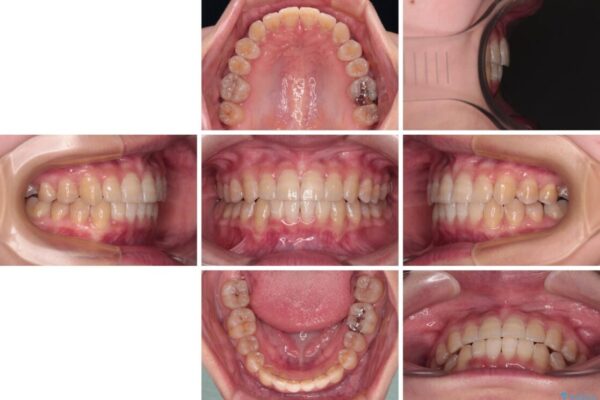

治療前、下顎前歯のデコボコが集中しており、奥歯の咬み合わせは、上顎に対して下顎が前方位にある状態でした。下顎の歯列を後方へ移動させる治療はインビザラインの得意とするところですので、1年程度で無事に治療を終えることができました。

治療後

• 【モニター】下顎前歯のデコボコをインビザラインできれいに 治療後画像